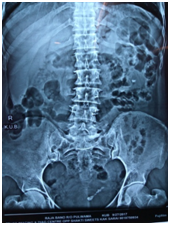

All patients who reported within 1-2 days of ureteric colic were examined, and subjected to Haemogram, KFT, Urine examination, Ultrasound and NCCT Scan (Figure 1&2) to document ureteric calculi at the time of colic with respect to location, side and size of the stone. Age and sex of the patient was noted down and SOADS regime was started for a period of 4 weeks maximum after which this MET was stopped. The routine follow up examination were performed, using the same tools to evaluate the success of the treatment after every week till 4 weeks of study period. Patients were instructed to discontinue the study medication after spontaneous stone expulsion and date of expulsion is to be recorded. For patients without stone in urinary tract on final USG/NCCT but unnoticed stone expulsion, the date of last positive stone status is to be recorded (Figure 3). For the children the dosage of the SOADS regime was half the dosage. Two - three litres of fluid which consists of Lemon juices, Oranges juices and clear water or Tea. This regime was continued for 2 weeks after which again assessment was made and if the stone did not pass then it was continued for another 2 weeks. Treatment was considered successful when stone was expelled within 4 weeks. After 4 weeks, patients who did not pass the stone were advised to undergo minimally invasive surgery depending upon the stone size and location.

Figure 1 X-ray KUB showing multiple lower ureteric calculi.